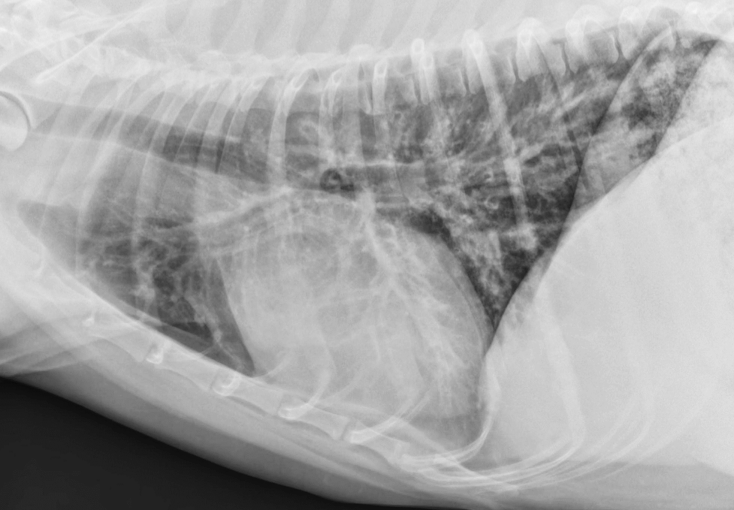

Lung Pattern?

Pneumothorax *Arrows = atelectasis*